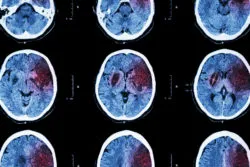

Drug manufacturers Biogen and AbbVie voluntarily withdrew Zinbryta from the market in April 2018 because of patient reports of swelling in the brain after using the drug. In a letter regarding the recall sent to health care providers in March, the drug makers referred directly to Zinbryta brain inflammation.

Encephalitis is swelling in the brain tissue itself, and meningoencephalitis is inflammation of the membranes that cover the brain. The majority of encephalitis incidents are caused by either a bacterial or viral infection.

A minimum of 12 cases of swelling of the brain have been linked to Zinbryta around the world. In three of those cases Zinbryta brain inflammation proved fatal.